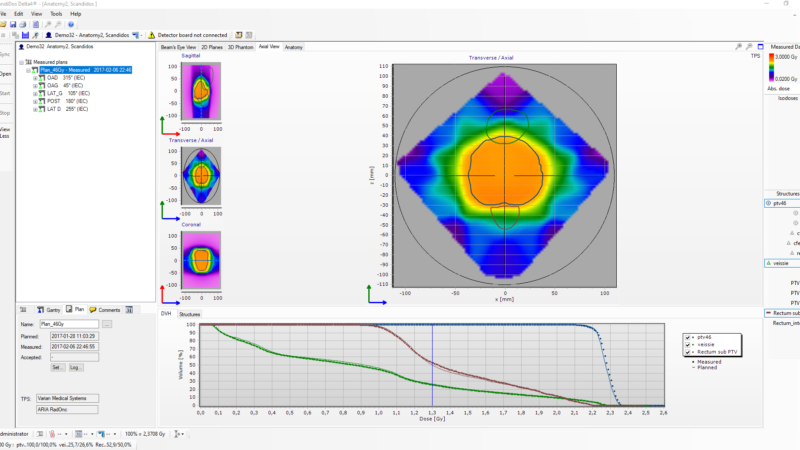

Delta4 software

Streamline your workflow

Delta4 software

Instant and accurate analysis

- Instant results in one place

- Powerful analytic tools

- Isocentric measurements in two orthogonal detector planes

- Resolution 5 mm at isocenter, can be increased to 2.5 mm by merging